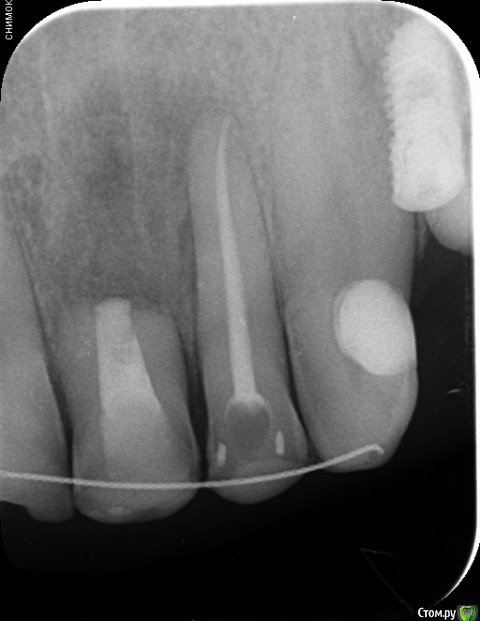

Astronaft Опубликовано 6 июля, 2018 Поделиться Опубликовано 6 июля, 2018 (изменено) Я пробовал один раз.Впечатления смешанные.1. просто в исполнении.2. Хорошо, быстро заживает. Есть ощущение что так можно проводить профилактику альвеолита.3 .Десны действительно достаточо.4. Кость - неоднозначно. Надо попробовать 2 рядом стоящих зуба "с шайбой" и "без".5. Шайба удаляется легко. Без анестетика, зондом поддел.6. Поверхность под шайбой - белая соед.тканная пленка. Рентген в день удаления -> фото через неделю -> фото через 2 месяца + КЛКТ ( срезы: перегородка и оба корня) http://miworks.weebly.com/uploads/1/6/8/7/16879370/x07221.jpg http://miworks.weebly.com/uploads/1/6/8/7/16879370/dscn6666_orig.jpg http://miworks.weebly.com/uploads/1/6/8/7/16879370/dscn6948_orig.jpg http://miworks.weebly.com/uploads/1/6/8/7/16879370/dscn6943_orig.jpg http://miworks.weebly.com/uploads/1/6/8/7/16879370/dscn6952_orig.jpg http://miworks.weebly.com/uploads/1/6/8/7/16879370/dscn6953.jpg http://miworks.weebly.com/uploads/1/6/8/7/16879370/dscn6954.jpg http://miworks.weebly.com/uploads/1/6/8/7/16879370/dscn6949_orig.jpg http://miworks.weebly.com/uploads/1/6/8/7/16879370/x07221-1.jpghttp://miworks.weebly.com/uploads/1/6/8/7/16879370/x07221-4.jpg http://miworks.weebly.com/uploads/1/6/8/7/16879370/x07221-2.jpghttp://miworks.weebly.com/uploads/1/6/8/7/16879370/x07221-3.jpg Изменено 6 июля, 2018 пользователем Astronaft 4 Ссылка на комментарий

annda Опубликовано 7 августа, 2018 Поделиться Опубликовано 7 августа, 2018 (изменено) Тоже попробовала.Застарелый перелом корня.Два свища на момент приема.Удаление всего,спилила на коронковом фрагменте до связки,канал закрыла IRMом,в дефект порошок Лилпласт на АPRF ,обратно фрагмент притопила,фиксация на ретейнер.Снимок через две недели.Теперь думаю,не длинноват ли фрагмент.Хотя,может и проекция снимка вводит в заблуждение.КТ срезы сняла с экрана,пардон за качество. Изменено 7 августа, 2018 пользователем annda 3 Ссылка на комментарий